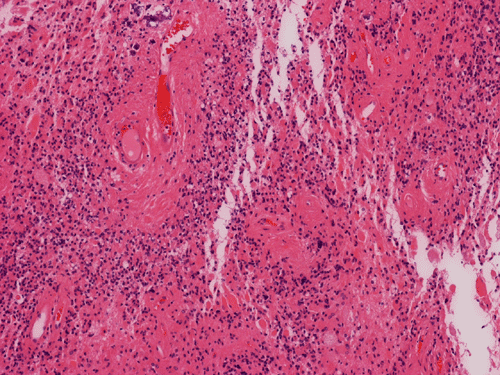

Pathology of the Case: MRI shows a large mass with the more solid component located in the lateral ventricles and the cystic component protruding into the cortical area. The solid area is enhanced (Panel A). On low magnification, the lesion has alternating area of high and low cellularity (Panel B) with scattered calcifications in some of the sections. Medium and high magnification demonstrates perivascular coronary arrangement of cytoplasmic processes (Panel C, D, and E). The nuclei are bland and mitotic figures are not readily seen. Randomly scattered brown pigment containing cells are found in multiple areas of the tumor (Panel F, G, and H). Scant lipidized cells with enlarged nuclei (Panel I) are also present. The tumor cells are strongly positive for glial fibrillary acidic protein (GFAP) (Panel J and K) and S100 protein but are negative for epithelial membrane antigen (EMA), neurofilament proteins, and NeuN. The overall Ki67 labeling is low but focal small areas (about the size of one high power field) has increased labeling. The pigment appears to be melanin on microscopic examination. These pigments are positive with Fontana-Masson stain (Panel L) but negative for Prussian blue stain for iron (Panel M). These features confirmed that these are melanin pigments. The pigment granules are positive for periodic acid-Schiff reaction (N), negative for Ziehl-Neelsen (acid fast) stain..